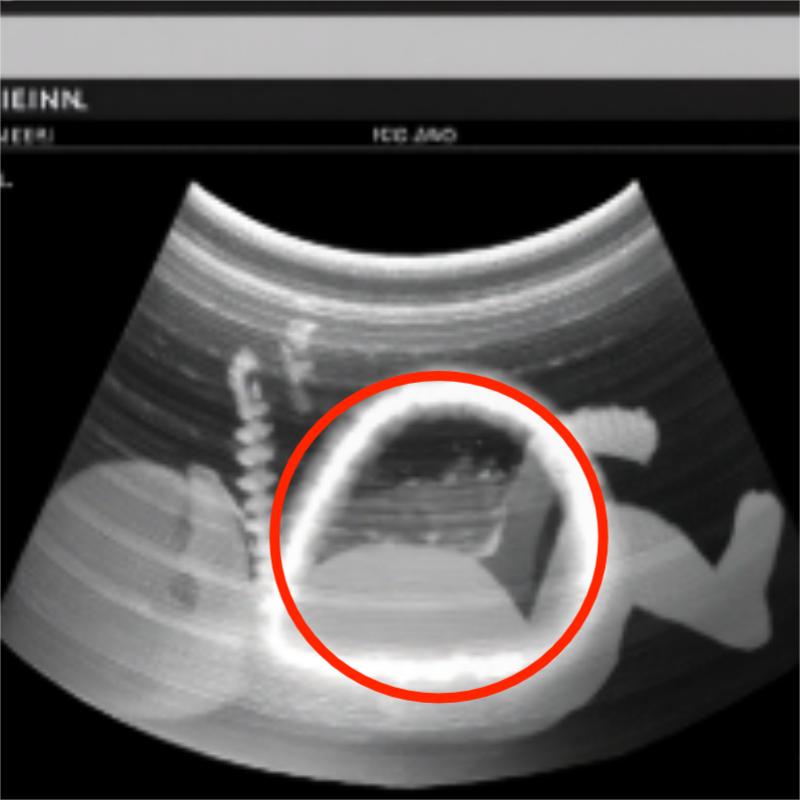

At home, we didn’t plan a nursery theme or fold tiny onesies into neat stacks. We learned new words. Neural tube. Sacral. Closure. We pinballed between hope and fear and strange, clinical brightness. I slept on my side, one hand on my belly, whispering to the small swimmer inside: I’m here. I won’t blink. I won’t miss a beat. David read studies aloud until the words became river sounds. The world narrowed to appointments, measurements, the architecture of weeks.The second scan was on a different machine, larger, its interface resembling a cockpit. The spine appeared again, white beads along a riverbank. The gap was still there—only now it seemed to shift, like a door trying to decide whether to be open or closed. The doctor adjusted angles, increased depth, changed probes.

“There’s an acoustic shadow interfering,” he murmured. “But we can’t assume artifact. We prepare for both.” He drew diagrams: delivery in a specialized unit, neonatal surgery if needed, the choreography of teams and minutes. I nodded, memorizing each step like a dance whose music I didn’t yet know. 💙

In the last scan—one more machine, one more monitor—the gap looked different. The sonographer frowning, then adjusting, then frowning again. “I need to try one thing,” she murmured. She repositioned our son on his side, lifted his tiny leg with astonishing gentleness, and angled the probe along a narrow corridor of sound. The image sharpened. The beads of the spine lined up, one after the other, unbroken. Where the darkness had opened before, light threaded through like a needle. The room stayed silent long enough for me to believe it, and then the sonographer laughed, a soft breath of disbelief.

“It’s not a lesion,” she said. “It’s an artifact. An acoustic shadow.”

The neonatologist exhaled with his whole body. The surgeon leaned in to confirm, tracing the white line with a gloved finger on the screen. “The shadow was cast by something maternal,” she said carefully, “likely the hardware from your scoliosis surgery years ago. The angles we used during pregnancy kept catching it right here.” She tapped the place where fear had lived for months. Relief did not arrive like a trumpet. It arrived like tidewater, slow and certain, pulling broken shells back to sea. I began to laugh and cry at once. David bent over our son’s blanket and whispered, “You trickster. You little comet.” 🌈